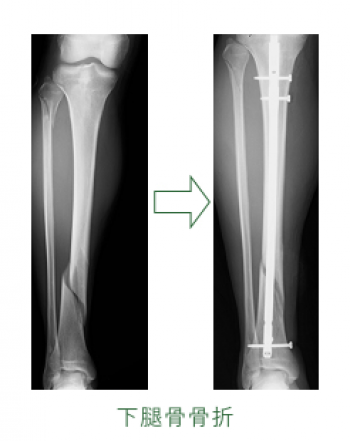

今日、ご紹介するのは、下腿骨骨幹部骨折についてご紹介していきます。

下腿骨骨幹部骨折

交通事故、スポーツ障害としてよくみる骨折です。

脛骨単独骨折ならび脛腓両骨骨折

脛骨単独骨折よりも脛腓両骨骨折が多い。

多くの骨折は脛骨中・下1/3の境界部に起こり、脛骨が骨折すると腓骨もこれに伴って骨折する。

開放性骨折になりやすく、骨癒合がしにくく、反張下腿などの変形を残すことが多い。